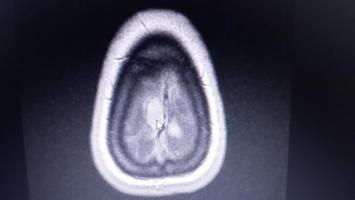

2021 roku w czerwcu rozpoznano u Patrycji Kościukiewicz:

- nowotwór o niepewnym charakterze opon mózgowo - rdzeniowych

Patrycja piszę: ,,Przez opieszałość służby zdrowia i brak działania muszę podjąć leczenie we własnym zakresie. Celem tej zrzutki jest w zasadzie pomoc dla mnie abym mogła poddać się prywatnego zabiegu kraniotomii, która jest podstawową metodą leczenia oponiaków, zwłaszcza przy zatoce strzałkowej."